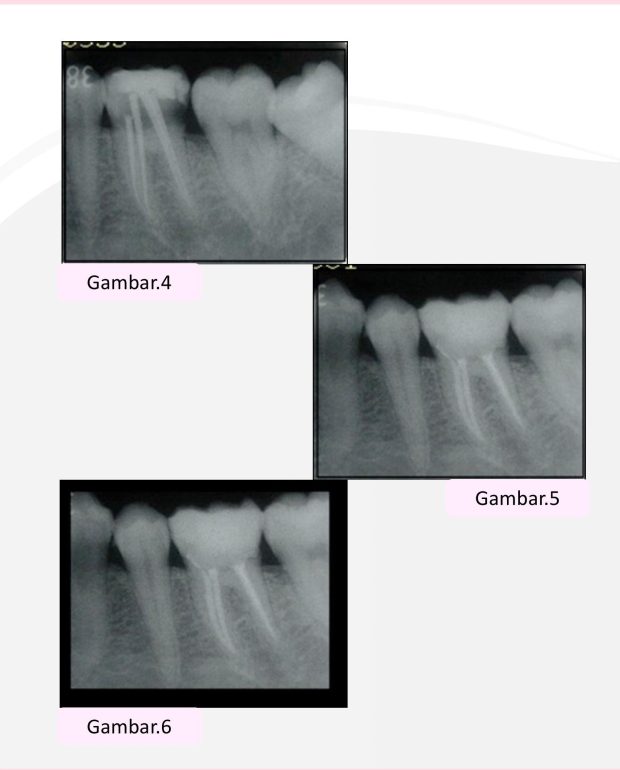

• Penempatan master cone dilakukan dan gambaran radiografi diambil (Gambar 4).

• Obturasi dilakukan dengan kombinasi teknik kondensasi lateral dan warm gutta percha menggunakan system B tip serta injeksi panas (Gambar 5).

• Dua belas bulan kemudian, pasien diinstruksikan untuk datang kembali. Dari pemeriksaan klinis didapatkan bahwa tidak ada lagi keluhan pada giginya dan hasil radiografi menunjukan jaringan periapikal yang normal (Gambar 6).